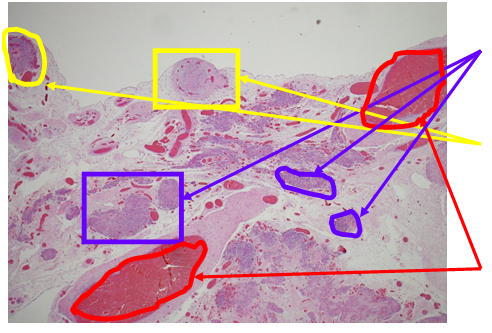

Pathology of the mass showed soft tissue with smooth muscle proliferation, fibrotic and decidual reaction (Figure 1 & 3). There was no evidence of malignancy. Sections show a low grade spindle cell proliferation, fascicular in appearance, forming small and large nodules. The spindle cells show no cytological atypia and no mitoses were identified. The nodules are situated in a fibrous and vascular background with interspersed collections of decasualized cells. The spindle cells are positive for smooth muscle action (SMA), and are negative for Melan-A and HMB-45. The findings, combined with the clinical presentation, are consistent with disseminated peritoneal leiomyomatosis (DPL). A leiomyoma arising from the serosal aspect of the uterus is also a consideration, though less likely (Figure 1 & 2).

Figure 1 Hematoxylin and Eosin Stain (H&E stain or HE stain).

1A: Smooth muscle arranged like leiomyomas = Leiomyomatosis (Purple Circles)

1B: Stromal cells resembling decidua (Light Purple),br>Vessels (red circles)